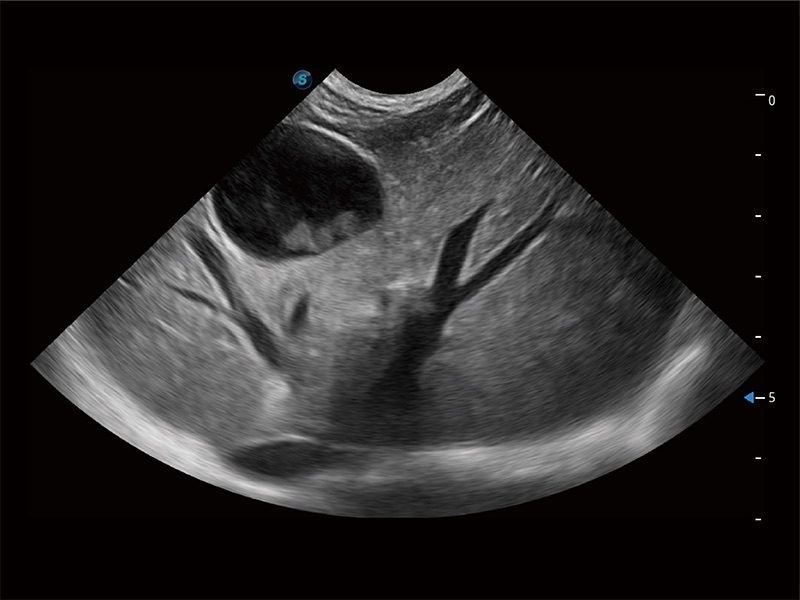

(犬)肝脏

(犬)胎儿主动脉弓立体血流

(犬)胎儿四腔心